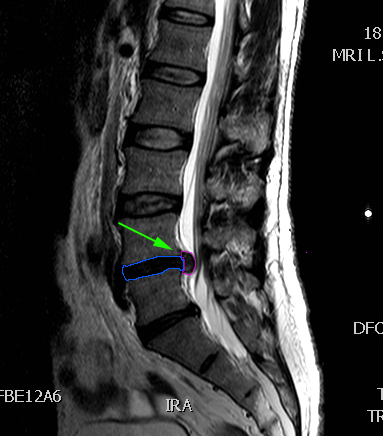

LumbarHernia8

Κήλη οσφυϊκού μεσοσπονδυλίου δίσκου, επίπεδο

Ο4-Ο5 (πράσινο βέλος)